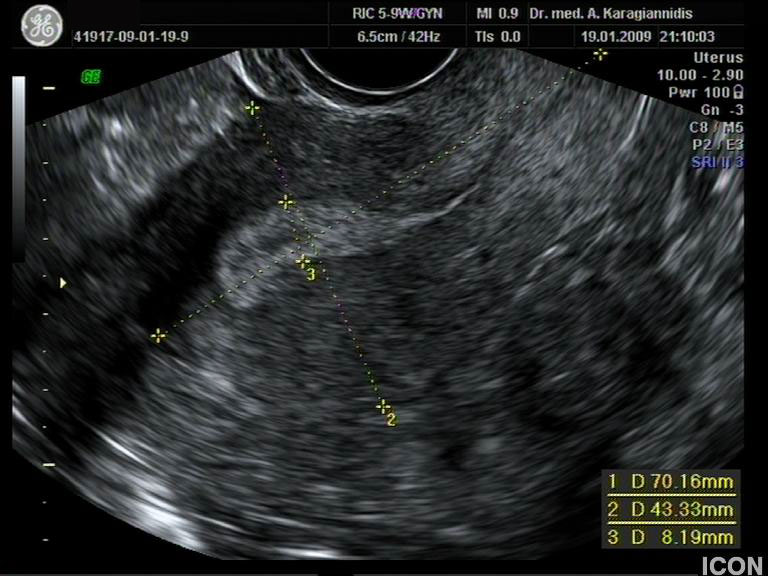

Ενδοκολπικός U/S έσω Γεννητικών Οργάνων

Αυχενική διαφάνεια

Η αυχενική διαφάνεια (ΑΔ) είναι η συλλογή υγρού στον τράχηλο του εμβρύου και συγκεκριμένα ανάμεσα στο δέρμα και στους ιστούς που καλύπτουν τη σπονδυλική στήλη.